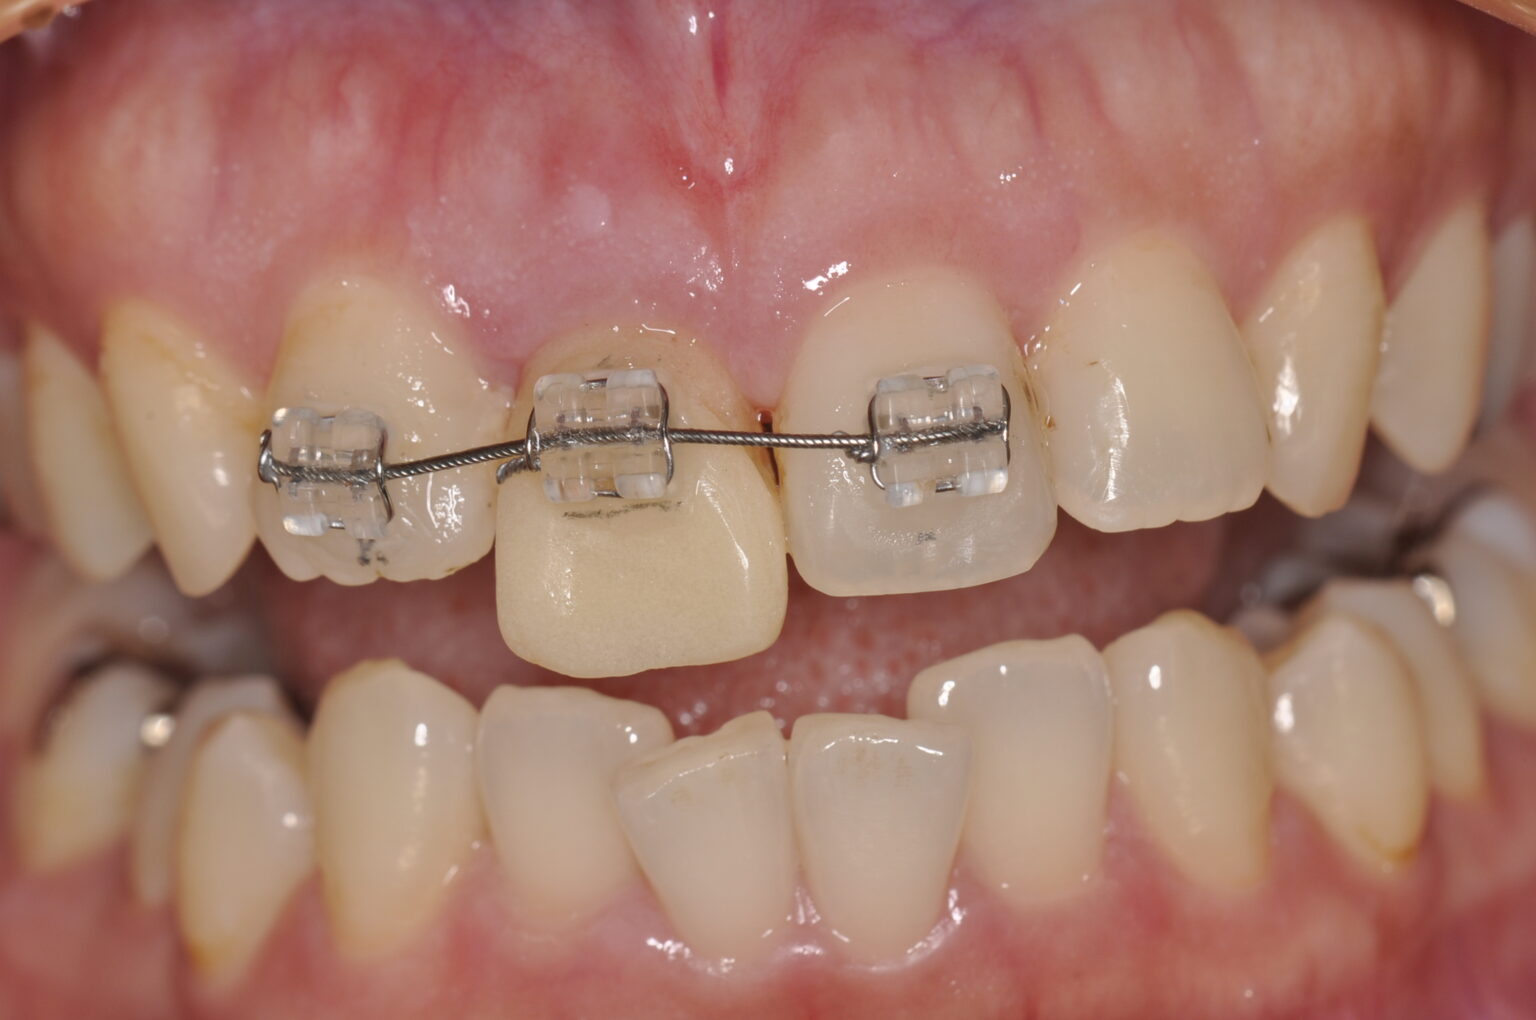

症例写真

後戻りも考え挺出を

オーバー目に。

使用装置

ブラケット装置